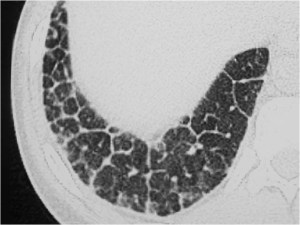

SIGNO DEL CASQUETE APICAL IZQUIERDO

La aparición de una densidad en el ápex pulmonar izquierdo, de borde inferior cóncavo y bien delimitado (casquete apical) en un paciente con traumatismo torácico, debe hacernos sospechar la existencia de una rotura aórtica.

Deben excluirse otras causas de casquete apical, especialmente las lesiones residuales tuberculosas, que suelen acompañarse de otros hallazgos como tractos fibrosos pleuro-parenquimatosos, pérdida de volumen en el lóbulo superior, granulomas, etc.

Mostramos un caso de rotura aórtica por accidente de moto. En este paciente también aparece el signo de la alteración del contorno aórtico.

En el corte de TC de tórax con contraste intravenoso del mismo paciente vemos la rotura aórtica (flecha verde), un hemotórax bilateral –algo más cuantioso en el hemitórax izquierdo- (flechas azules) y un hematoma mediastínico (flecha naranja).